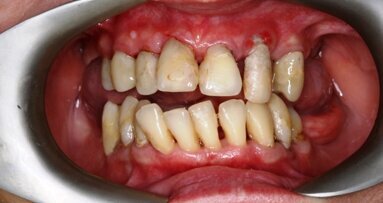

_agresywne zapalenie przyzębia (Ryc. 2a i b), występujące przed 45 r.ż.,

Radiografia obu klinicznych sytuacji obrazuje zaawansowany etap choroby. Te 2 przypadki różnią się przede wszystkim wiekiem pacjenta, który ma 25 lat w przypadku agresywnego zapalenia przyzębia (Ryc. 2a i b) i 68 lat w przypadku chronicznego zapalenia przyzębia (Ryc. 3a i b).